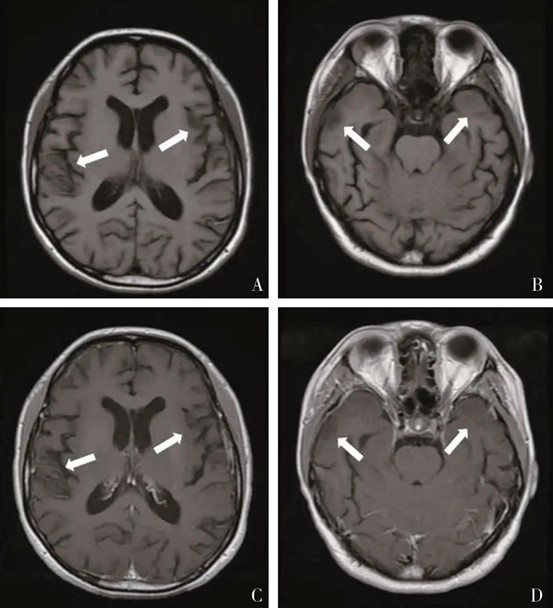

头部MRI示:双侧颞叶白质信号异常,脑萎缩;双侧额叶、侧脑室旁白质区域异常信号灶,考虑脱髓鞘灶;双侧颞叶对称性白质异常信号增强后强化程度低于正常脑白质(图1)。

图1:患者头部MRI A、B示双侧颞叶可见对称性白质异常信号,伴有脑萎缩征象;C、D示双侧颞叶对称性白质异常信号增强后强化程度低于正常脑白质。